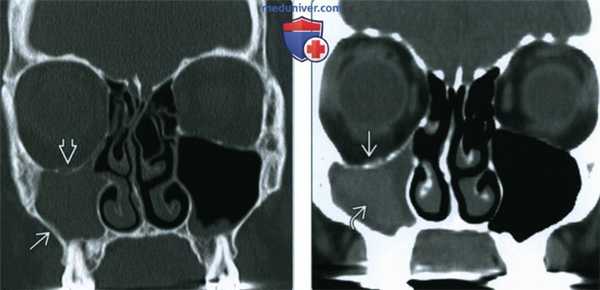

(Слева) При корональной «костной» КТ у пациента с СНП определяется снижение пневматизации правой верхнечелюстной пазухи и легкое утолщение ее наружной стенки. Дно орбиты смещено книзу, объем орбиты увеличен, что типично для СНП. На энофтальм указывает относительное заднее положение глазного яблока.

(Справа) При корональной КТ без КУ определяются типичные признаки СНП: уменьшение объема правой верхнечелюстной пазухи, низкое положение дна орбиты и заднее положение ипсилатерального глазного яблока. В пазухе определяется плотное хроническое отделяемое.

(Слева) При корональной «костной» КТ определяются типичные признаки СНП. Снижена пневматизация уменьшенной в объеме правой верхнечелюстной пазухи. Дно орбиты смещено книзу, общий объем орбиты увеличен.

(Справа) При корональной МРТ Т1ВИ С+ у пациента с энофтальмом справа определяется уменьшение объема и снижение пневматизации верхнечелюстной пазухи, заполненной «выветренным» содержимым. Дно ипсилатеральной орбиты смещено книзу.